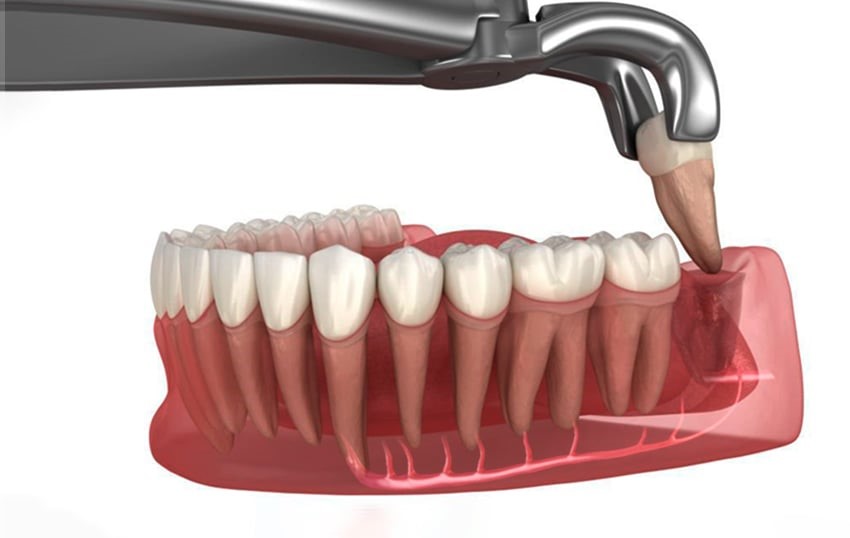

Tiến hành nhổ răng khôn

-

Gây tê cục bộ

Thực hiện trong phòng vô trùng

Áp dụng kỹ thuật ít xâm lấn, hạn chế tổn thương mô mềm